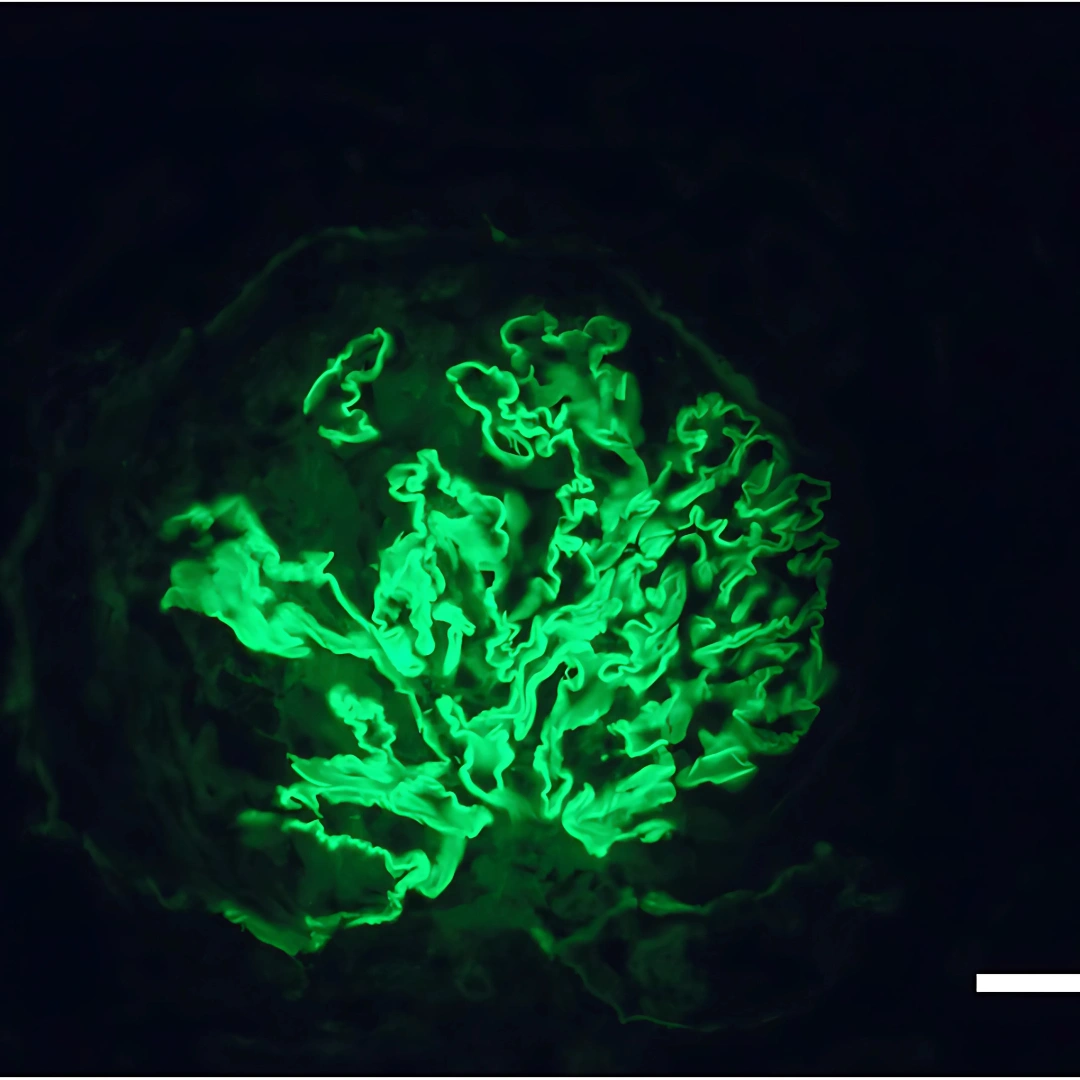

- Cancer Test

- Cancer Test